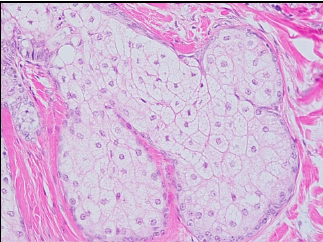

8

Q

A

• sebaceous gland

• simple branched acinar